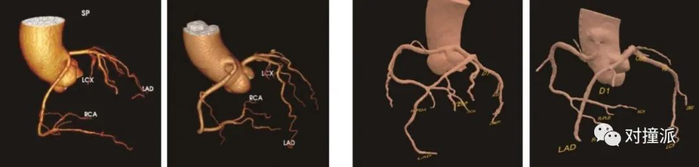

与肺部CT不同的是,心血管CT影像,需要医生自己手动将二维图像进行三维重建,还原心脏结果和血管走向分布,再运用电子标尺测量血管狭窄,并进行其它指标的分析。

AI将重建和测量的过程自动化,省去了医生大量重复劳动的精力。这既减轻工作压力,也提高效率,成为了医生日常使用顺手的工具。数坤介绍,目前在北京的安贞医院,医生的软件使用率接近100%。

“以前,要求符合心内科的习惯,进行左右心冠图像的分开重建,需要人工去干预,现在通过自动化的软件,非常便捷地做到这一步,这是目前数坤做的非常好的自动化功能,对我来说比较惊喜。”上海市第六人民医院放射科副主任医师张佳胤,在论坛上提及使用体验。

数坤软件的冠状动脉重建